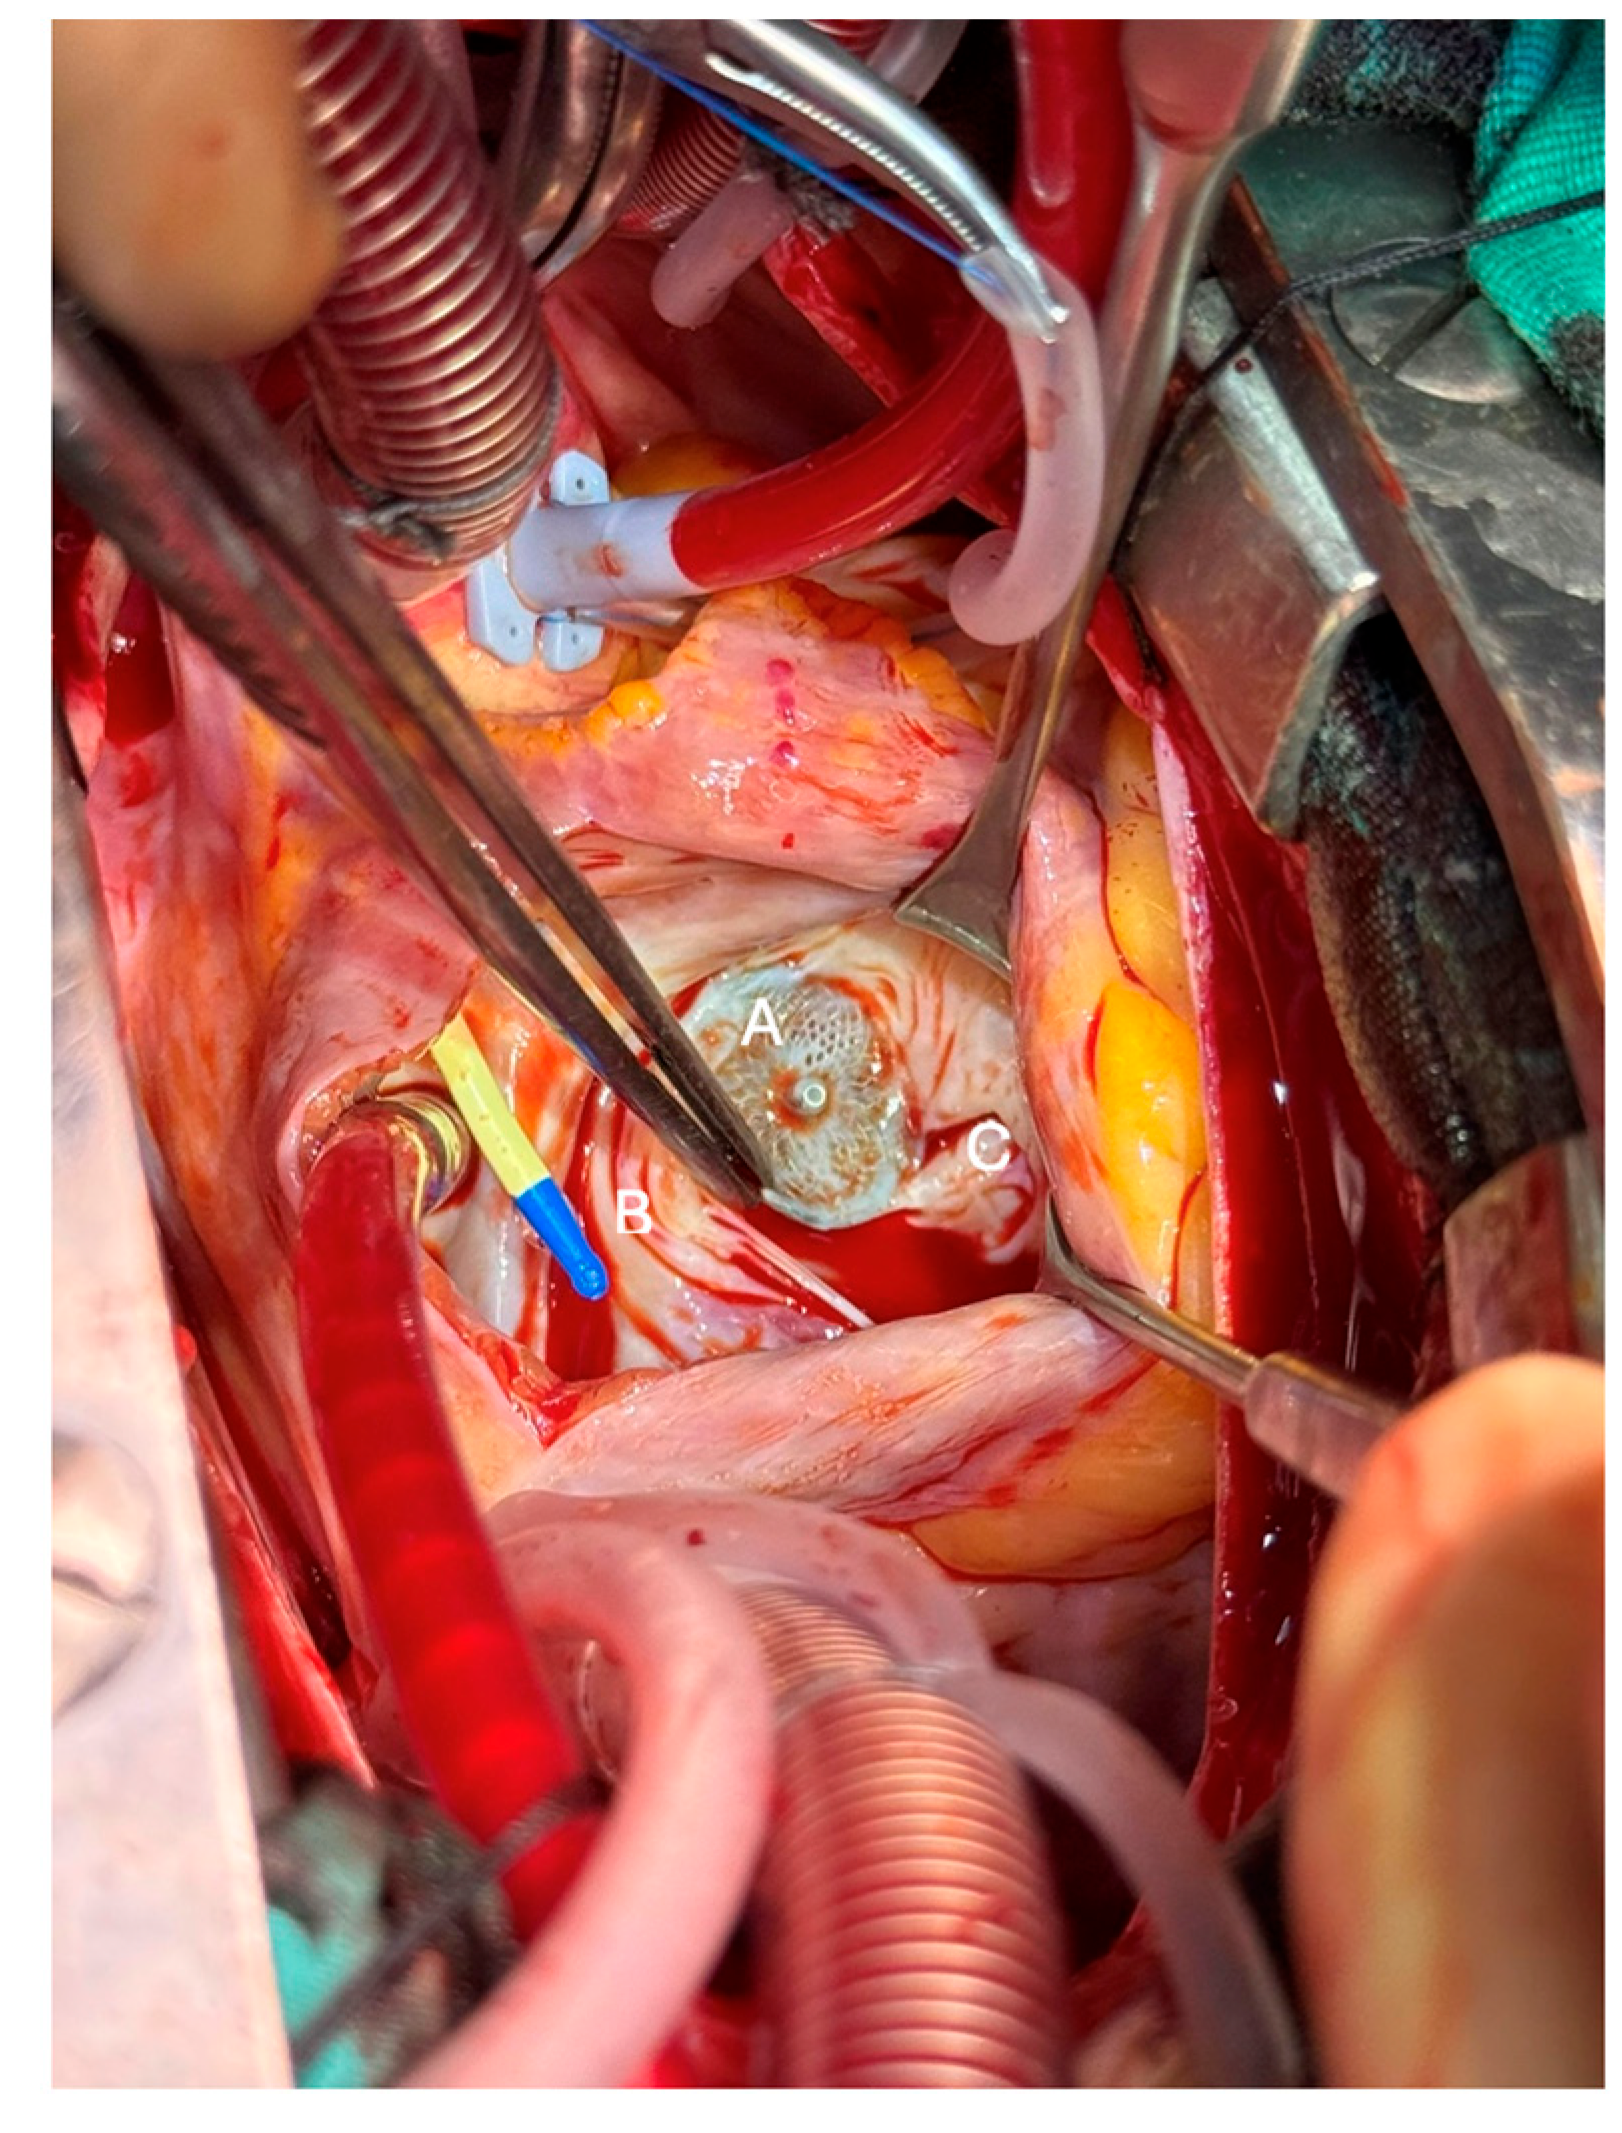

The patient underwent tricuspid valve repair with Kay annuloplasty under cardiopulmonary bypass 20 months after pmVSD closure, with minimal anticipated risk of future annular restriction; studies showed preserved annular growth and satisfactory tricuspid valve function [6]. Intraoperative findings provided direct evidence of the mechanisms underlying this progression. Entrapment of the anterior and septal tricuspid leaflets, displacement of papillary muscles to the periphery, and fibrosis across the perimembranous septum were seen. These changes impaired the continuity of right ventricular inlet–outlet flow and promoted obstruction and regurgitation. Surgical excision of fibrotic tissue and pericardial patch augmentation restored valve competency and unobstructed flow. The intraoperative lesions, including device–valve adhesions and fibrotic bands, are demonstrated in Fig. 1. Fibrotic tissue, seen in Fig. 2, arising from the anterior leaflet papilla, which impeded the continuity between the right ventricular inlet and outlet, was excised, and the defect on the tricuspid valve was subsequently reconstructed (augmented) using an autologous pericardial patch. Notably, the surgical assessment confirmed that the device was stable, properly positioned, and not protruding into or directly narrowing the RVOT. Therefore, removing the device and patching the VSD was unnecessary due to the recognized risk of atrioventricular conduction disturbance associated with device explantation. Instead, targeted resection of fibrotic tissue and tricuspid valve reconstruction effectively restored RVOT patency and valve function. The patient was weaned from bypass uneventfully, and intraoperative TEE confirmed mild tricuspid regurgitation with complete relief of the obstruction. The postoperative course was uncomplicated.

Figure 1: Intraoperative image from right atriotomy view showing interaction of the MFO device (A) with the anterior and septal leaflets of the tricuspid valve. Entrapment of leaflets that are pushed to the periphery by the device (B) and associated displacement of papillary muscles (C) are demonstrated.